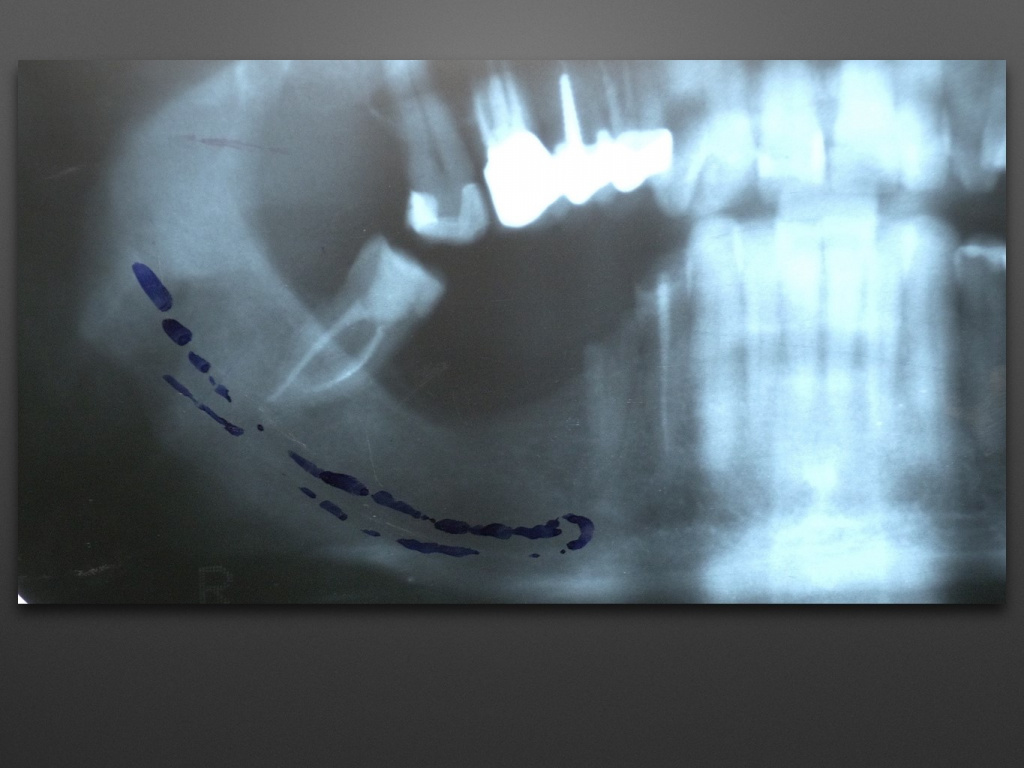

Горизонтальное увеличение альвеолярного отростка (остеоматрикс, биоимплант ГАП + пластина)